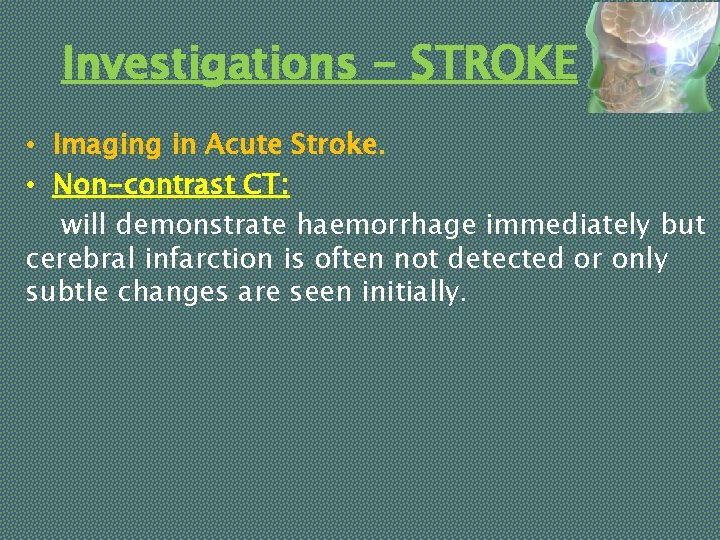

Investigations - STROKE • Imaging in Acute Stroke. • Non-contrast CT: will demonstrate haemorrhage immediately but cerebral infarction is often not detected or only subtle changes are seen initially.